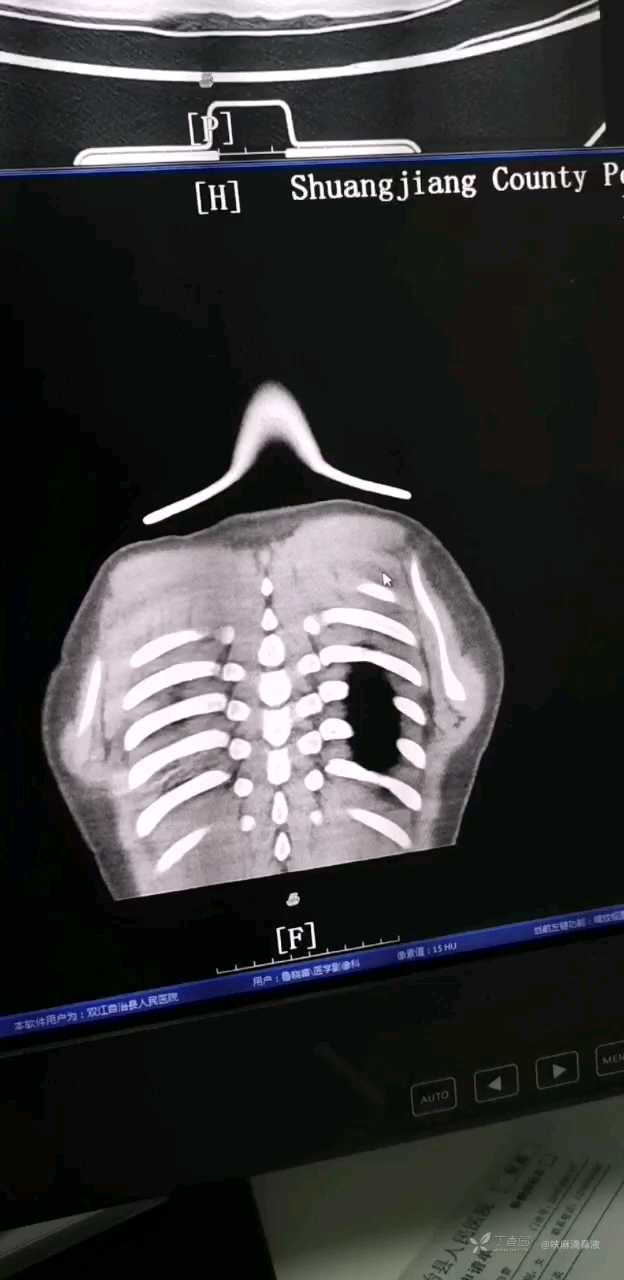

术前CT

病史:患儿9岁,2022-06-04 13时左右误吸笔帽,误吸后临沧市云县人民医院就诊,行CT检查考虑右下肺异物残留,因云县人民医院手术条件有限,建议患儿转双江县人民医院手术。

救治过程:患儿到院后立即开通绿色通道,急诊复查CT(详见术前CT),结合患儿误吸史,查体,CT检查,考虑肺内异物,简化复杂流程,直接送手术室全麻下纤支镜下行异物取出,本院专家(朱伟红,原成都医科大学附属医院科主任)带领团队在纤支镜下取出笔帽。最终异物成功丶完整取出,患儿脱离危险。

术前报告: